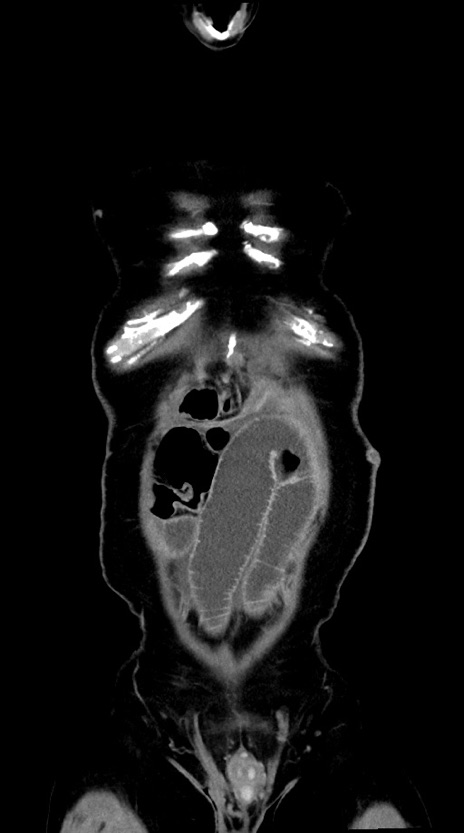

症例28(冠状断像)

【症例】60歳代男性

【主訴】嘔吐

【現病歴】胃癌にて胃全摘後。食思不振が悪化し、夜中に嘔吐することがある。

【既往歴】胃癌、胃全摘、脾摘、胆摘後

【データ】WBC 5900、CRP 10.56